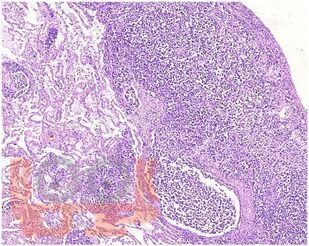

В атласе представлены авторские снимки макро- и микропрепаратов, демонстрирующих проявления канцероматозного лимфангита. В цветных иллюстрациях в описании макро- и микропрепаратов сделан акцент на наиболее важных макроскопических и гистологических изменениях, позволяющих диагностировать и дифференцировать канцероматозный лимфангит. Микропрепараты подготовлены Завьяловой М.В.